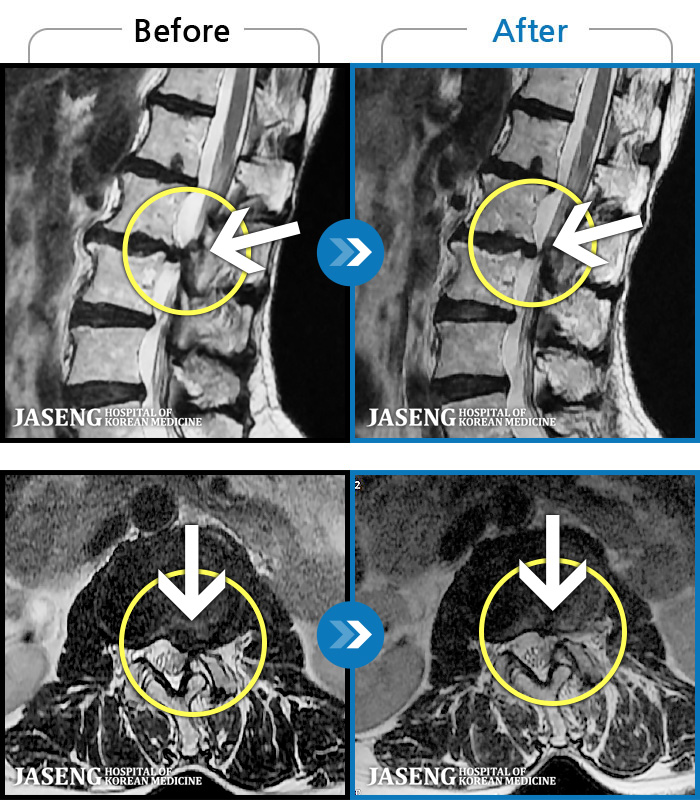

MRI ġ

1,299 MRI ũ ʸ Ȯϼ.